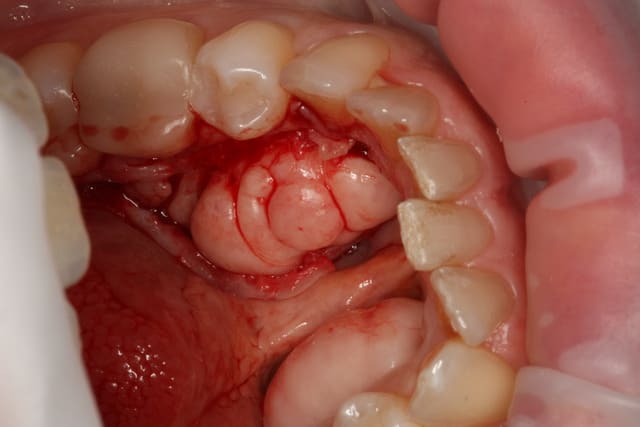

Sur photo 3 et 4, on voit l'os exposé, après lambeau de décollement.

Incision sur le sommet des tori, incision de décharge en mésial.

Section osseuse en 3 blocs, puis remodelage de la zone avec pam droite et très grosse fraise ronde,

sutures (ablation de surplus de tissu mou au besoin)